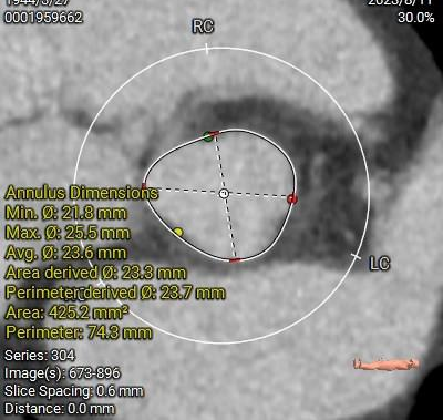

主动脉根部径线:

Annulus23.7mm

LVOT23.6mm

L28.4*R27.4*N28.8

SOVP89.9mm

STJ26.6mm

AA31.9mm

LV39.8mm

LV40.6mm

多平面分析:

Sub-223.8mm

Super-223.7mm

Super-425.2mm

Super-624.3mm

Super-825.4mm

Super-1025.4mm

双侧冠脉开口高度可,左侧瓣叶略长,预估左侧冠脉遮挡风险较低: